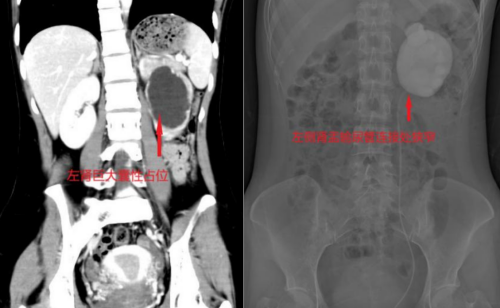

“肾积水?”这个陌生的词让张柔心里一沉。她立即来到香港马会app

泌尿外科门诊就诊。CT三维重建清晰显示,她的左侧肾盂被尿液撑得像一个巨大水囊,肾皮质已被压迫变薄;而进一步的“逆行尿路造影”明确了病因——肾盂与输尿管连接的“关口”出现严重狭窄,造影剂通过艰难,上游的肾脏已长期“泡”在积液中。

“你的腰痛很可能就是积水导致肾脏撑大、包膜受牵拉引起的。”医生指着影像耐心解释,“这个狭窄就像水管源头打了个死结,水排不出去,肾脏长期‘憋着’,功能会慢慢受损。”